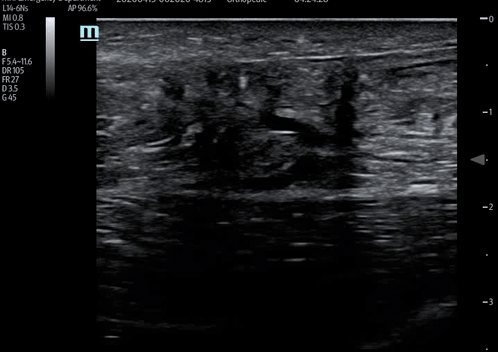

Achille’s tendon long axis - demonstrating rupture with hypoechoic areas within the tendon representing the tear with surrounding oedema/blood.